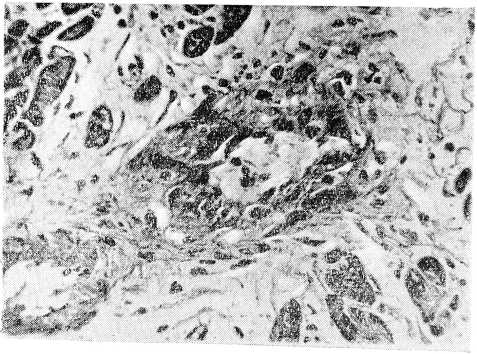

Рис. 2. Гломерулонефрит при болезни Шенлейн — Геноха

Микроскопическое исследование. Почка — большая часть клубочков увеличена в размерах за счет пролиферации эндотелия и накопления лейкоцитов в просветах сосудистых петель; увеличенные клубочки почти целиком выполняют просветы капсул. Некроз части сосудистых петель. Отдельные клубочки деформированы, имеют лопастную форму, бедны клеточными элементами и частично фиброти- зированы. Отмечается очаговое утолщение капсулы клубочков и образование полулуний. Дистрофия эпителия мочевых канальцев, в просвете их цилиндры и кровь. Набухание и фибриноидный некроз стенки мелких артерий и артериол почки, пролиферация эндотелия. Местами разрастание межуточной соединительной ткани. В интерсти- ции почки видны круглоклеточные и лейкоцитарные инфильтраты, расположенные преимущественно вокруг клубочков и мелких артерий. Местами лейкоциты инфильтрируют стенки мелких артерий, образуя вокруг последних значительные муфты. Сердце: Деструкция стенки мелких артерий и артериол миокарда с разволокнением и набуханием, а местами и фибриноидным некрозом, пролиферацией эндотелия и образованием небольших адвентициальных клеточных муфт. Селезенка: множественные мелкие очажки некроза в пульпе, редукция фолликулов, местами картины эндопериваскулита. Стенка пищевода: небольшие язвы слизистой оболочки. В подслизистом слое и в ад- вентиции пищевода мелкие артерии в состоянии фибриноидного некроза, а местами и полной деструкции с широкими эозинофильными муфтами вокруг них. Резкое умень- щение просвета и утолщение стенки некоторых сосудов, встречаются тромбы в различной стадии организации. Стенка кишки: обширные кровоизлияния в подслизистом и мышечном слоях, местами пропитывание кровью всей стенки, пролиферация эндотелия капилляров с почти полным стиранием их просвета. Пролиферация эндотелиальных клеток и адвентициальных элементов стенки мелких артерий и вен. Встречаются периваскулярные лейкоцитарные инфильтраты.

В данном случае нефрит, по-видимому, возник у больного на первых этапах заболевания (до вторичного поступления в терапевтическое отделение). Обращает на себя внимание быстрота развития процесса в почках с исходом в начинающееся сморщивание на протяжении сравнительно короткого периода времени. И в этом случае абдоминальный Синдром с бурным желудочно-кишечным кровотечением и анемизацией больного повлек за собой лапаротомию. К патологоанатомическим особенностям случая, кроме поражения почек, относятся распространенные васкулиты с фибриноидным некрозом стенки сосудов, особенно выраженные в миокарде и пищеводе; периваскулярные инфильтраты в стенке пищевода состояли преимущественно из эозинофилов, что, наряду с фибриноидным некрозом стенки сосудов, может служить указанием на аллергический характер поражения.